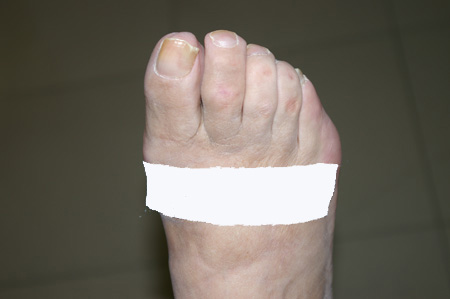

Imatge real pre-operatòria